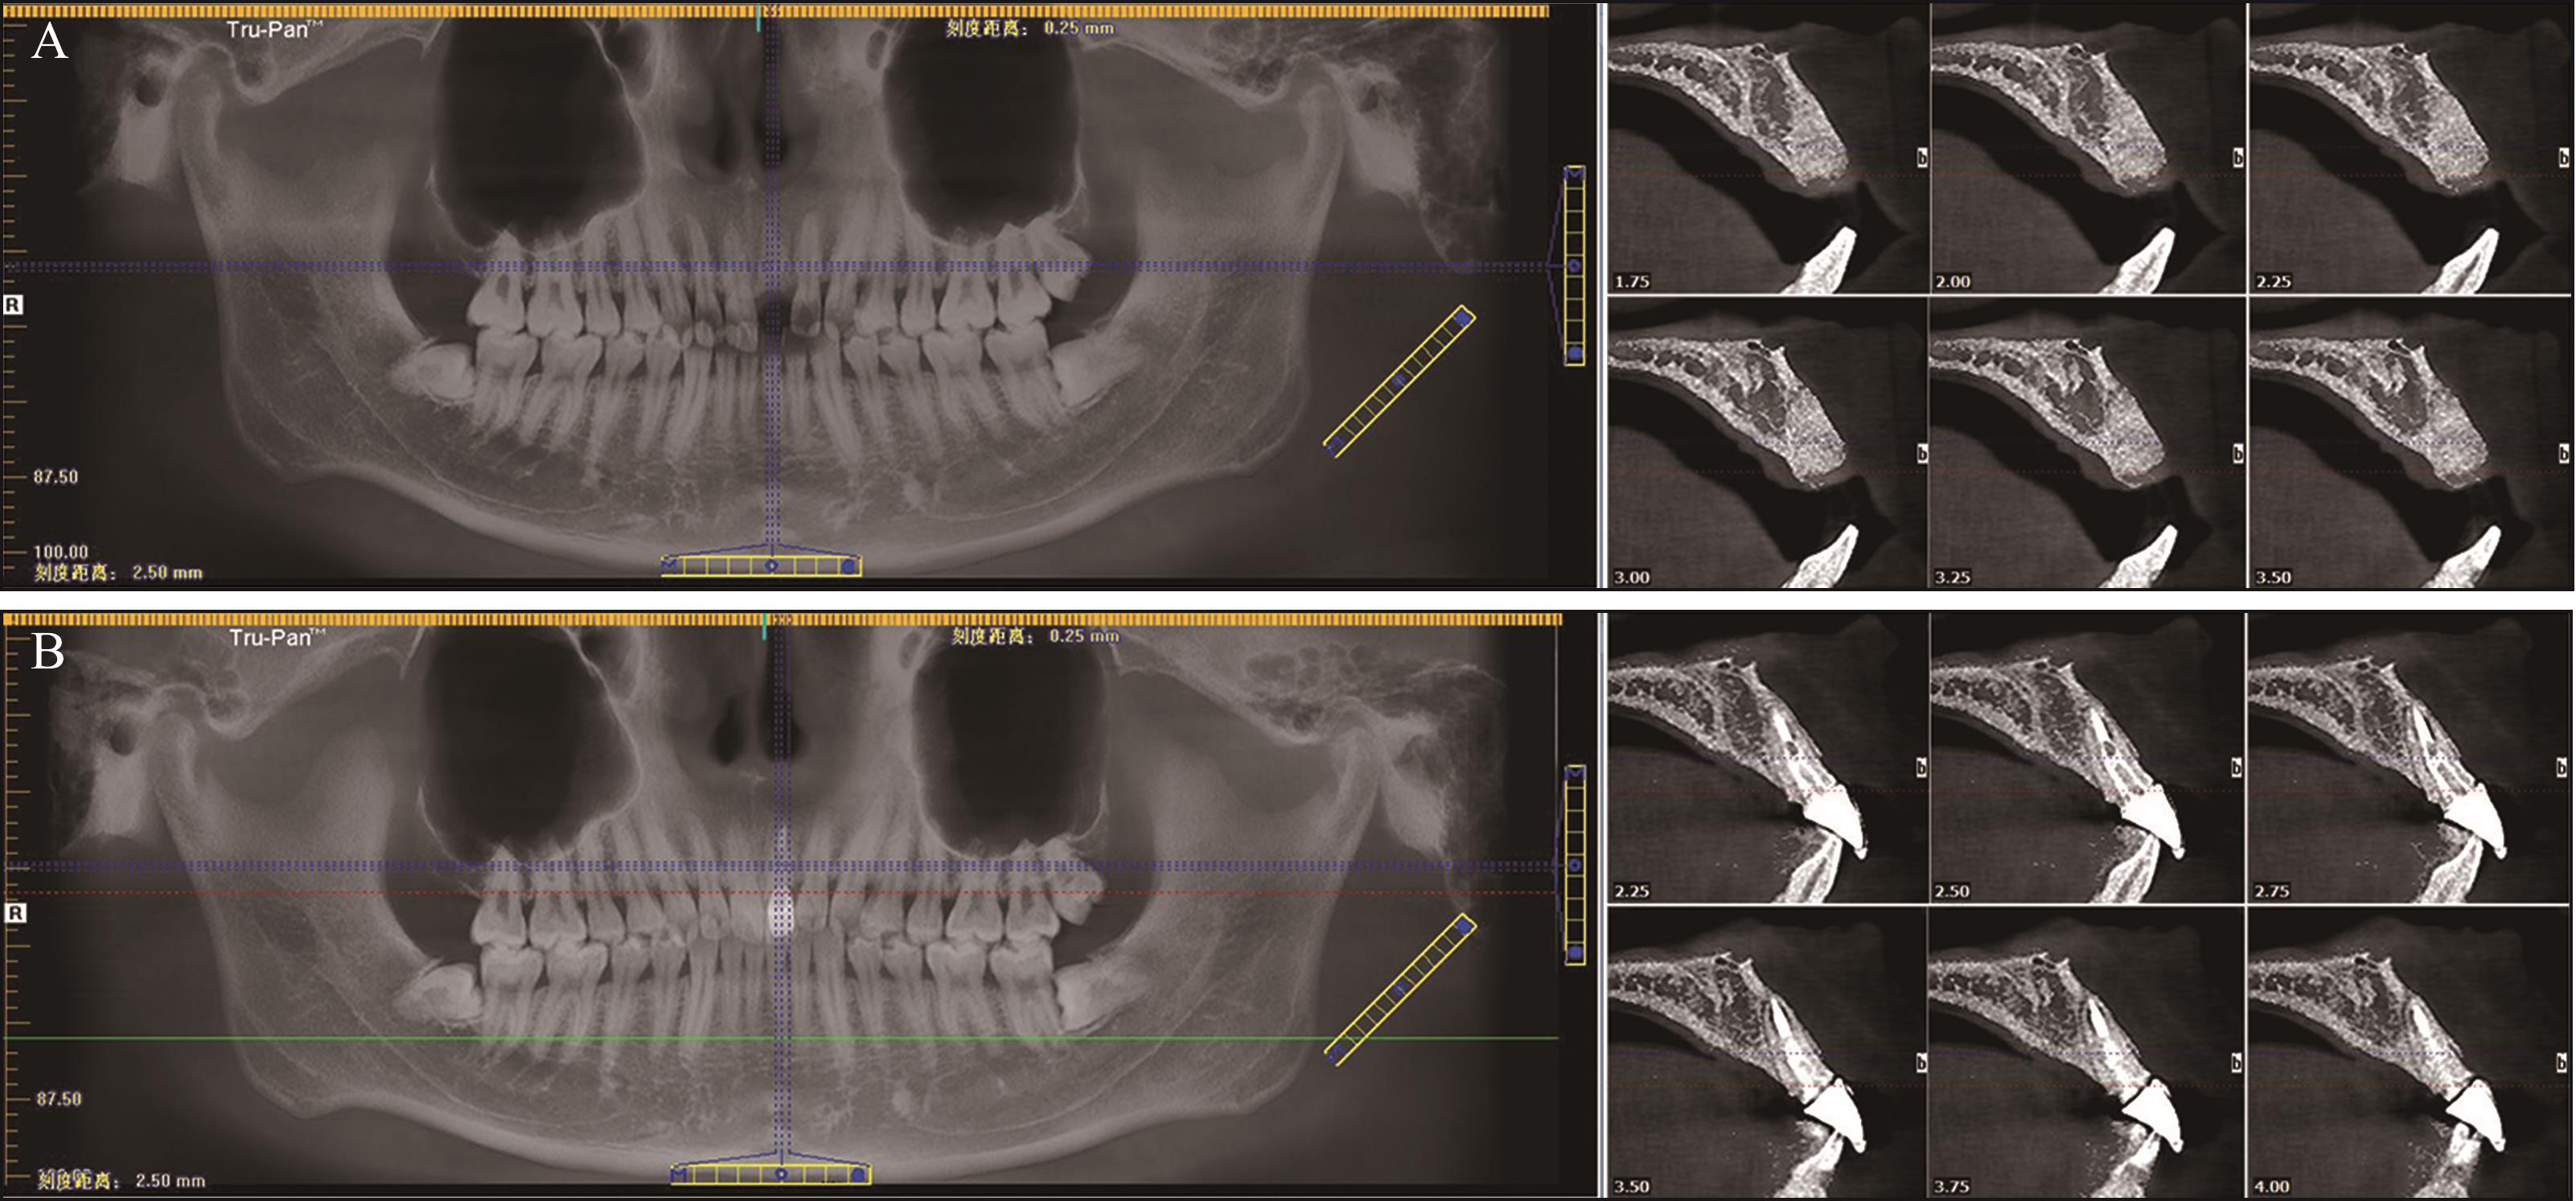

目的 比较浓缩生长因子(CGF)膜和Bio-Gide®胶原膜,分别与Bio-Oss®黏性骨联合用于上前牙牙槽嵴保存术(ARP)的临床效果。 方法 选取30例上前牙拔除后需要行ARP的患者,随机分为Bio-Gide组和CGF组。2组均在拔牙窝内严密充填Bio-Oss®黏性骨。Bio-Gide组用Bio-Gide®胶原膜覆盖于Bio-Oss®黏性骨上缘并封闭拔牙窝,CGF组用CGF膜覆盖并封闭拔牙窝。对比2组术后10 d软组织愈合情况,术后即刻及6个月牙槽嵴骨宽度及高度变化,以及术后6个月医患满意度。 结果 术后6个月,2组牙槽嵴骨宽度及高度变化差异无统计学意义(P>0.05)。但CGF组术后软组织愈合情况及医患满意度方面表现更优,差异有统计学意义(P<0.05)。 结论 与Bio-Gide®胶原膜相比,CGF膜与Bio-Oss®黏性骨联合应用可使上前牙ARP术后软组织愈合更好、医患满意度更高。

Objective To compare the clinical effects of concentrated growth factor (CGF) membrane and Bio-Gide ® collagen membrane, combined with Bio-Oss ® sticky bone respectively in alveolar ridge preservation (ARP) of maxillary anterior teeth. Methods Thirty patients who needed alveolar ridge preservation after maxillary anterior tooth extraction were selected and randomly assigned to the Bio-Gide group and the CGF group. In both groups, the extraction sockets were tightly filled with the Bio-Oss® sticky bone. In the Bio-Gide group used Bio-Gide® collagen membrane to cover the upper edge of the Bio-Oss® sticky bone and closed the wound. The CGF group, the CGF membrane was covered on the upper edge of the Bio-Oss® sticky bone and the wound was closed. The soft tissue wound healing status at 10 days after ARP, the changes in alveolar ridge height and width immediately after ARP and at 6 months after ARP, and the doctor-patient satisfaction at 6 months after ARP were compared and evaluated between the two groups. Results At 6 months after ARP, there was no statistically significant difference in the changes of alveolar bone width and height between the two groups (P>0.05). However, the CGF group showed better performance in soft tissue healing after ARP and doctor-patient satisfaction, and the differences were statistically significant (P<0.05). Conclusion Compared with the Bio-Gide® collagen membrane, the combined application of CGF membrane and Bio-Oss® sticky bone can lead to better soft tissue healing after ARP of maxillary anterior teeth and higher doctor-patient satisfaction, showing obvious advantages in ARP of maxillary anterior teeth.